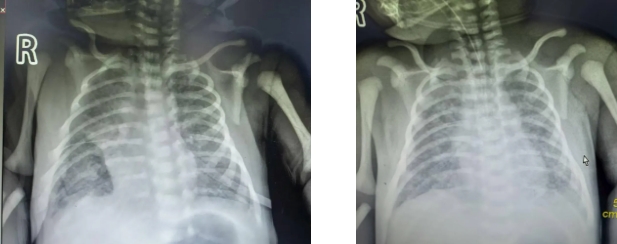

患儿因“羊水Ⅲ°浊、窒息复苏后呻吟、呼吸费力”入院。出生时Apgar评分1分钟7分,出生后出现严重呼吸窘迫及低氧血症,入院后的血气分析提示存在严重低氧血症和二氧化碳潴留,重度呼吸性酸中毒。胸片显示双肺斑片状阴影,符合重度MAS。此病例病情危重,进展迅速,救治难度大,给我院新生儿科带来了严峻的挑战。